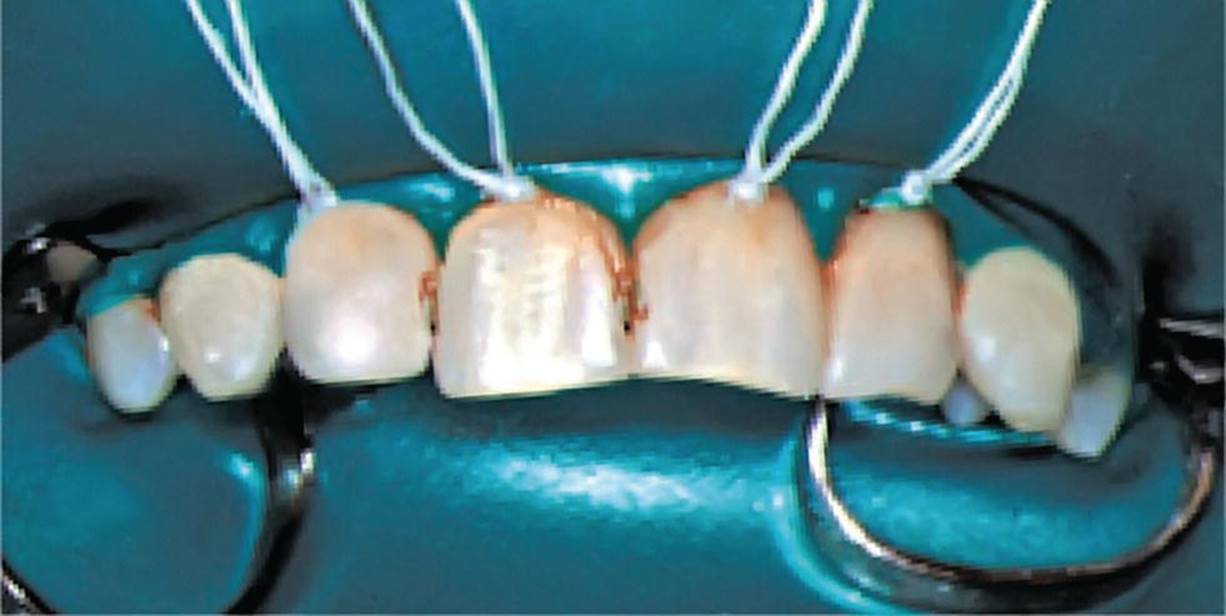

The procedures for applying a rubber dam in two common situations are described in Box 12.6 and illustrated in Figures 12.12 and 12.13. In the first example, the main purpose is to isolate the operation field in the posterior quadrant during the procedures of drilling and filling primary molar teeth (Figure 12.12). The second example is the upper front region where the main objective is to keep the operation field dry (Figure 12.13).

Figure 12.13 Rubber dam for isolating and drying the operation field before restorative therapy of maxillary incisors.